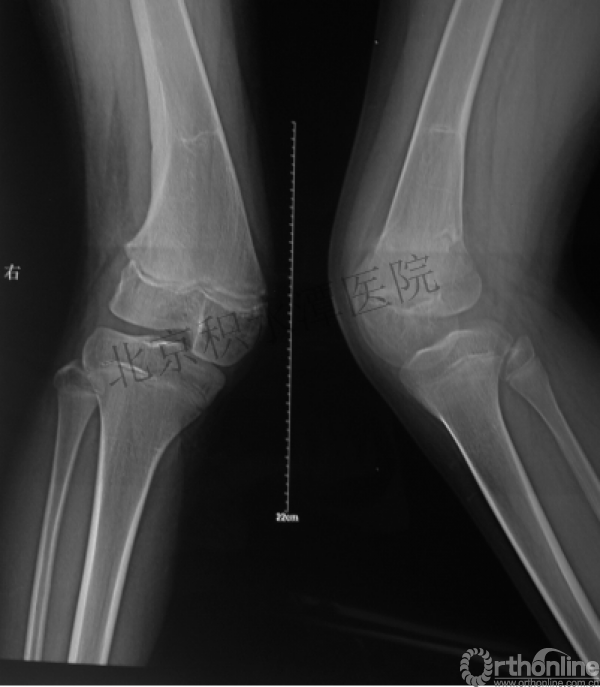

髁上骨折

跨骺板固定

伤后4年